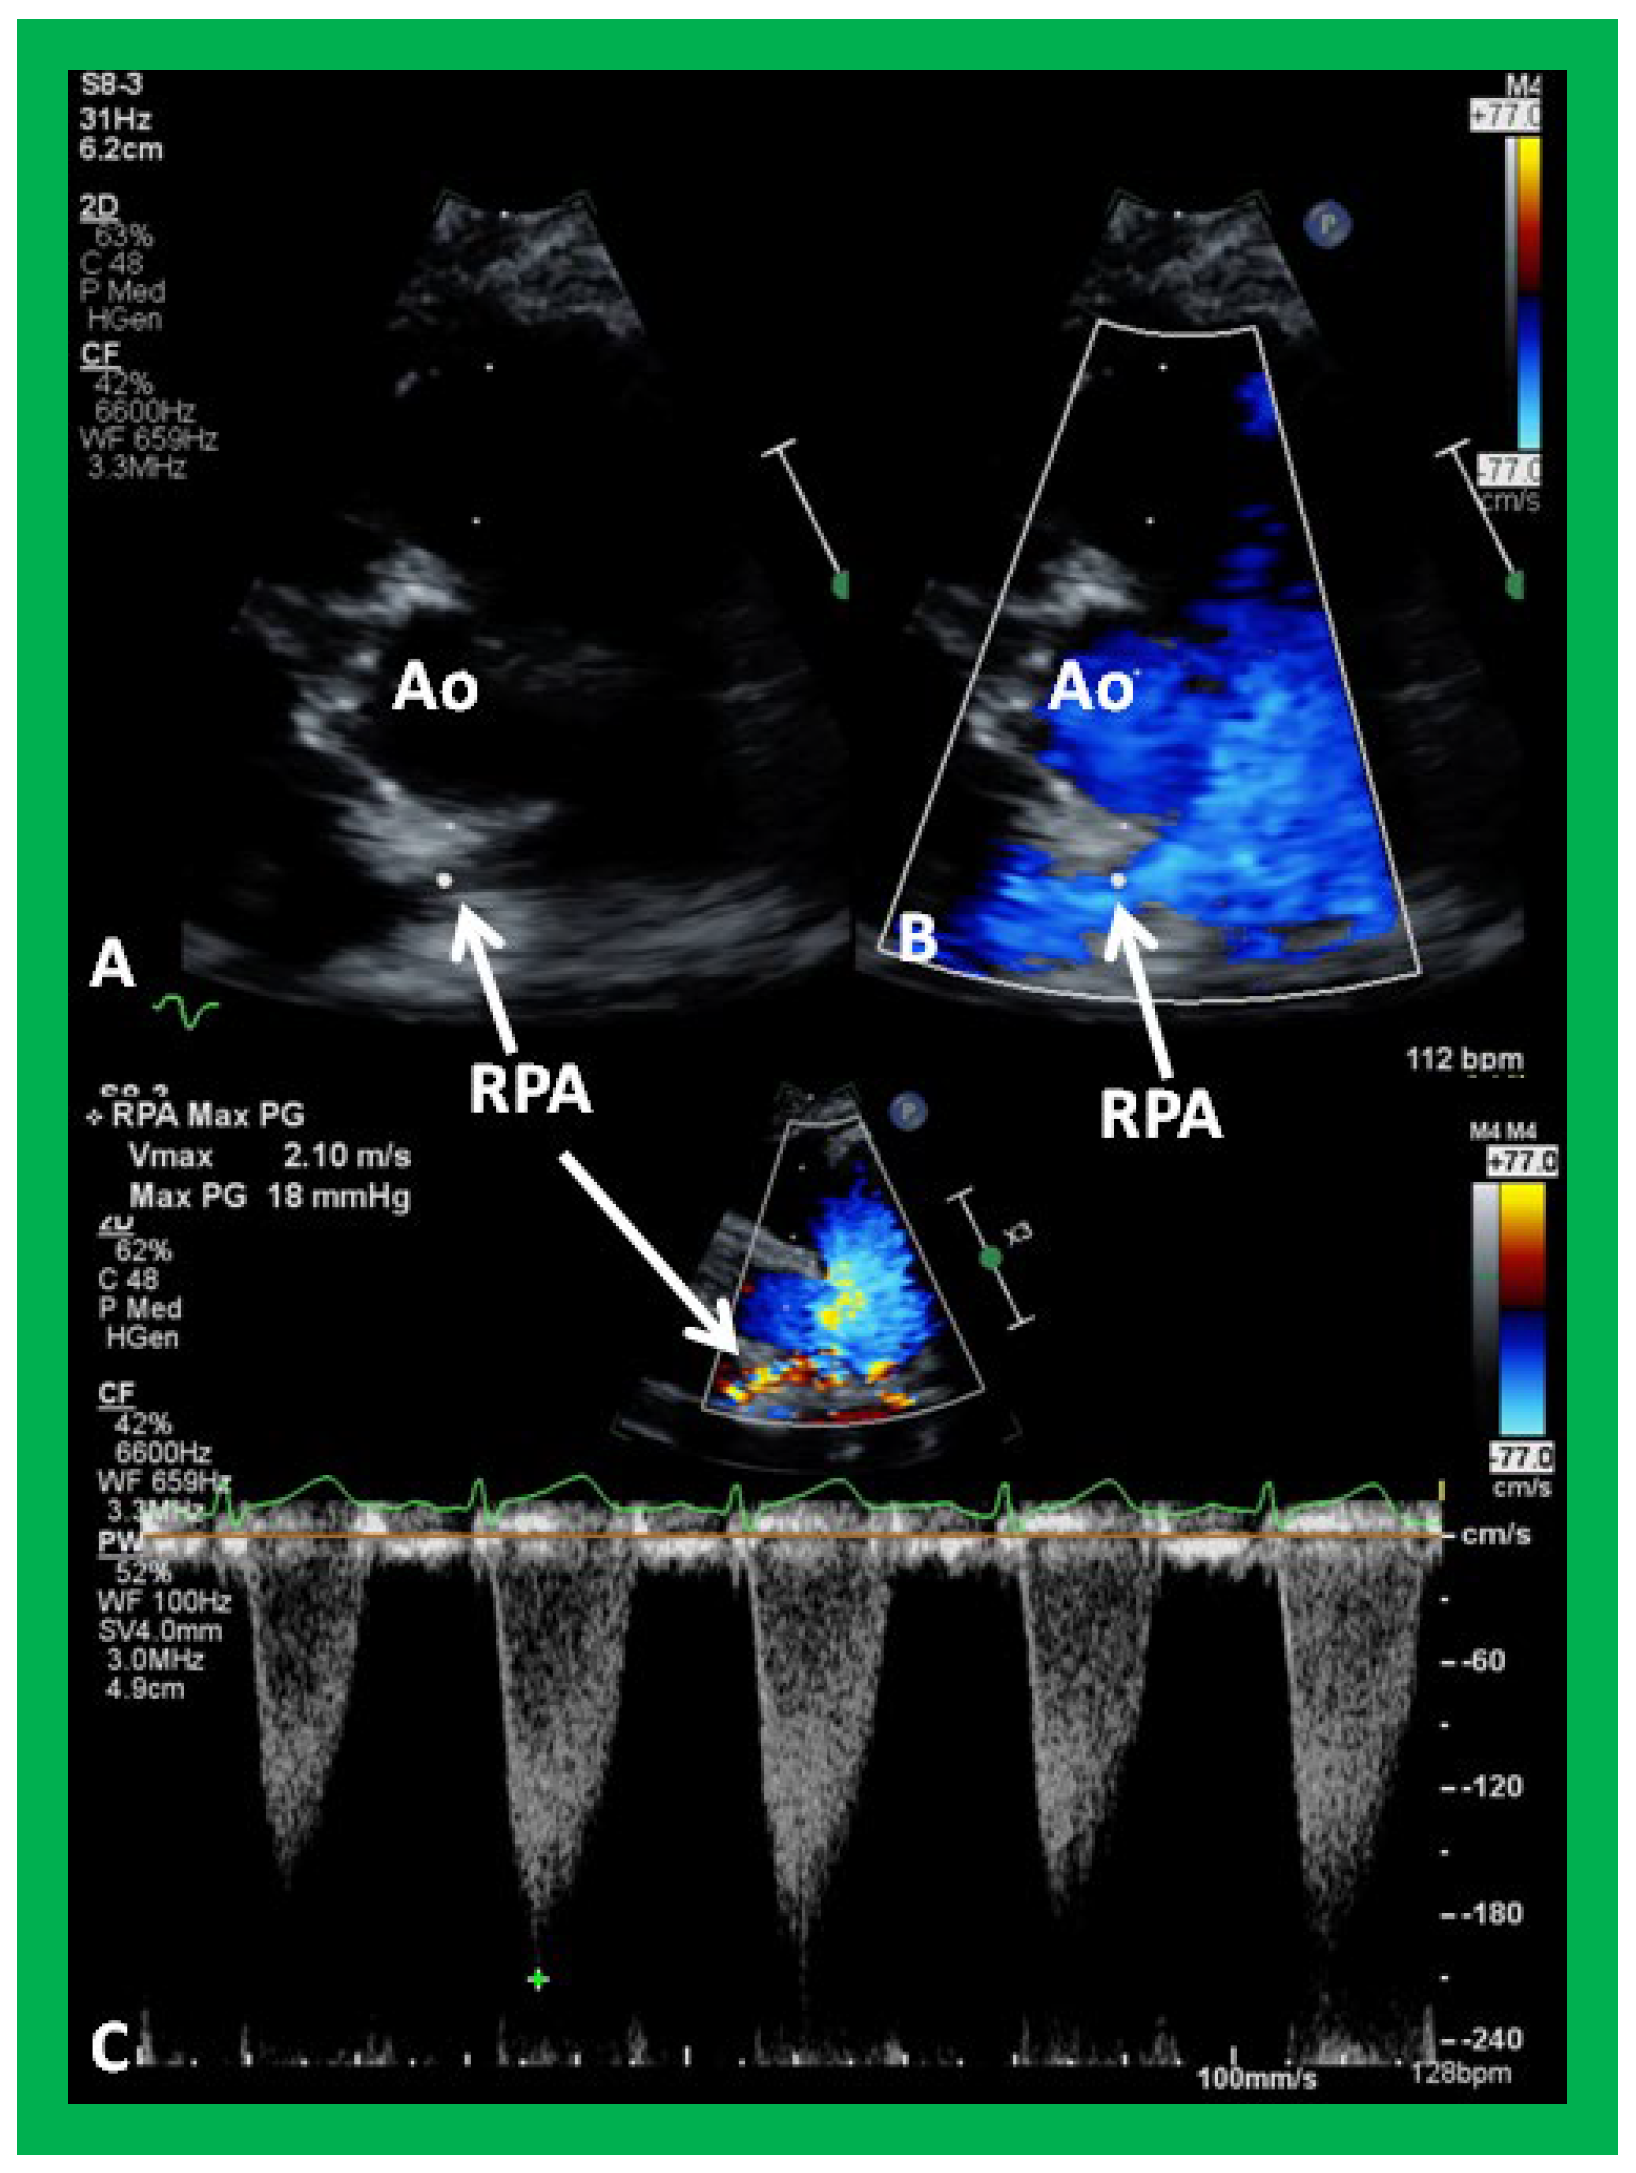

Distortion or stenosis of the branch PAs may be secondary to palliative procedures performed at the time of initial presentation or may have developed spontaneously in the innate branch PAs. The careful 2D and Doppler interrogation of PAs should be undertaken to detect significant stenosis (Figure 34) or hypoplasia (Figure 35) and, if present, balloon angioplasty, stent implantation or surgery as deemed appropriate should be undertaken [38].

Figure 34. Selected video frames from parasternal short axis view demonstrating stenosis of the right pulmonary artery (RPA) by two dimensional (A) and color (B) and pulsed (C) Doppler imaging. Doppler calculated gradient was 18 mmHg (C). Ao, aorta.